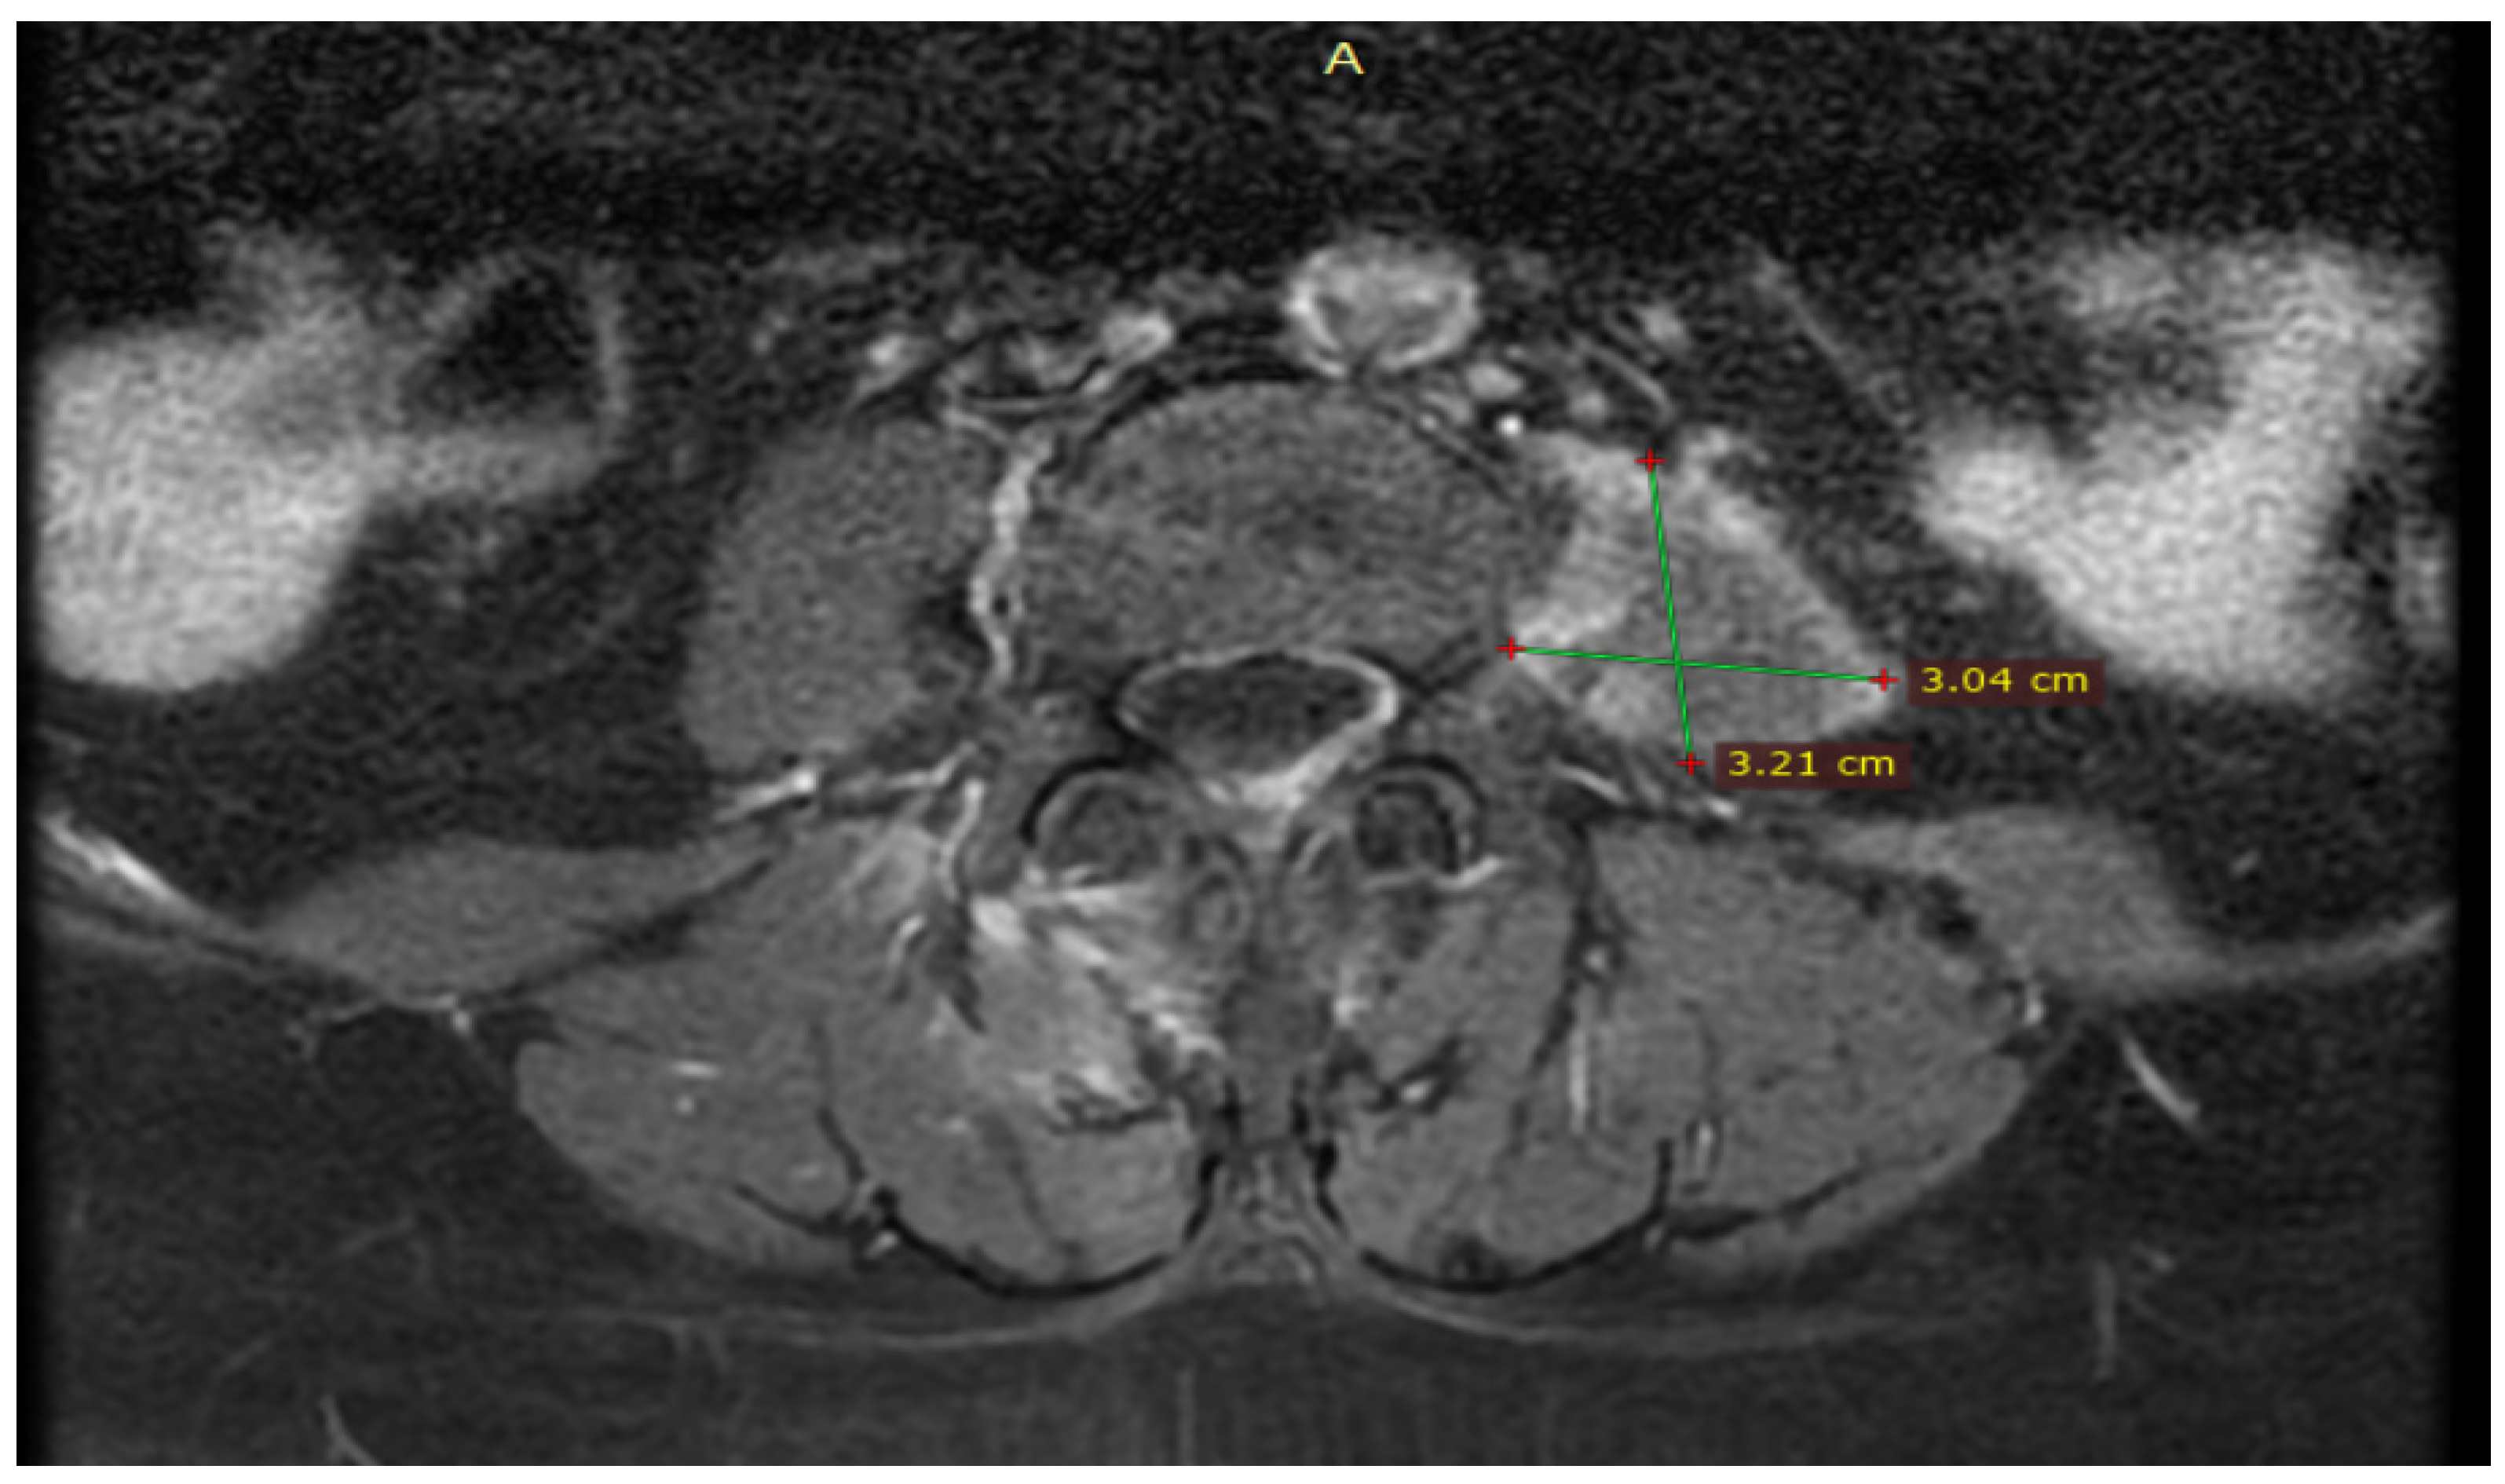

The patient performed an abdominal ultrasound, which revealed multiple gallstones, but the central bile duct was in a normal range value (Figure 1), so acute cholangitis was initially suspected.

Figure 1.

Abdominal ultrasound images of the gallbladder showed lithiasis (two calculi of 1.68 cm and 1.29 cm) associated with acoustic shadows in the transverse plane.